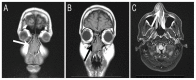

Imaging of a 42-year-old male patient with excessive nasal bleeding and a suspected nasal tumour. A & B: Computed tomography scans confirming the intact nasal bony wall (arrows). C: Magnetic resonance imaging showing increased T2 signals in the nasal cavity alone (arrow), without intracranial spread or extension to the sinuses.